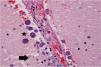

Estudio histológicoEn el examen microscópico se evidenció una congestión vascular generalizada siendo los órganos más alterados los pulmones, que mostraban además neumonía necrosante bilateral (fig. 2). En éstos y también en los riñones, el hígado y la tiroides se identificaron muy ocasionales quistes ovalados con abundantes estructuras basófilas redondeadas o semilunares en su interior, que también se identificaron de forma libre, asociados o no a focos de necrosis (fig. 3). Estas estructuras eran muy numerosas en el sistema nervioso central (fig. 4) y mostraban positividad para PAS, plata, Giemsa y un anticuerpo frente a protozoos (anticuerpo policlonal que se obtuvo mediante la inmunización de conejos a partir de un antígeno de Leishmania infantum, zimodeme MON-1), cuya especificidad es baja y puede mostrar una expresión positiva en otros protozoos intracelulares como el toxoplasma (fig. 5). Con estos hallazgos el diagnóstico de sospecha fue toxoplasmosis diseminada que se confirmó mediante la PCR. Además, se identificaron imágenes de hemofagocitosis en la médula ósea y un hemangioma esplénico infracentimétrico.

La toxoplasmosis puede tener una presentación morfológica variable describiéndose focos de necrosis como el hallazgo histopatológico más consistente en todos los órganos13,14. El diagnóstico se basa en la identificación del toxoplasma como estructuras basófilas alargadas o semilunares, más pequeñas que un hematíe y que pueden encontrarse en forma de taquizoitos sueltos o de quistes intracelulares rellenos de bradizoitos15. Cuando se encuentran en un bajo número su identificación puede ser muy difícil por lo que una tinción inmunohistoquímica puede resultar de ayuda13. Acostumbran a ser más numerosos en el cerebro ya que es el sitio más común de enquistamiento del parásito15. El diagnóstico diferencial morfológico cabe hacerlo con otros microrganismos intracelulares como histoplasma, las inclusiones intracitoplasmáticas del citomegalovirus y amastigotes de Leishmania o tripanosoma. La plata metanamina es positiva en los 2 primeros y permite apreciar la gemación del histoplasma, el citomegalovirus mostraría además inclusiones intranucleares. Los amastigotes, por su parte tienen un kinetoplasto, aunque éste es difícil de ver en los cortes histológicos por lo que la sospecha morfológica debería confirmarse mediante un anticuerpo IHC específico16 u otra técnica como la PCR.